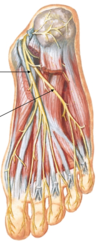

Label:

- nerve: superficial fibular